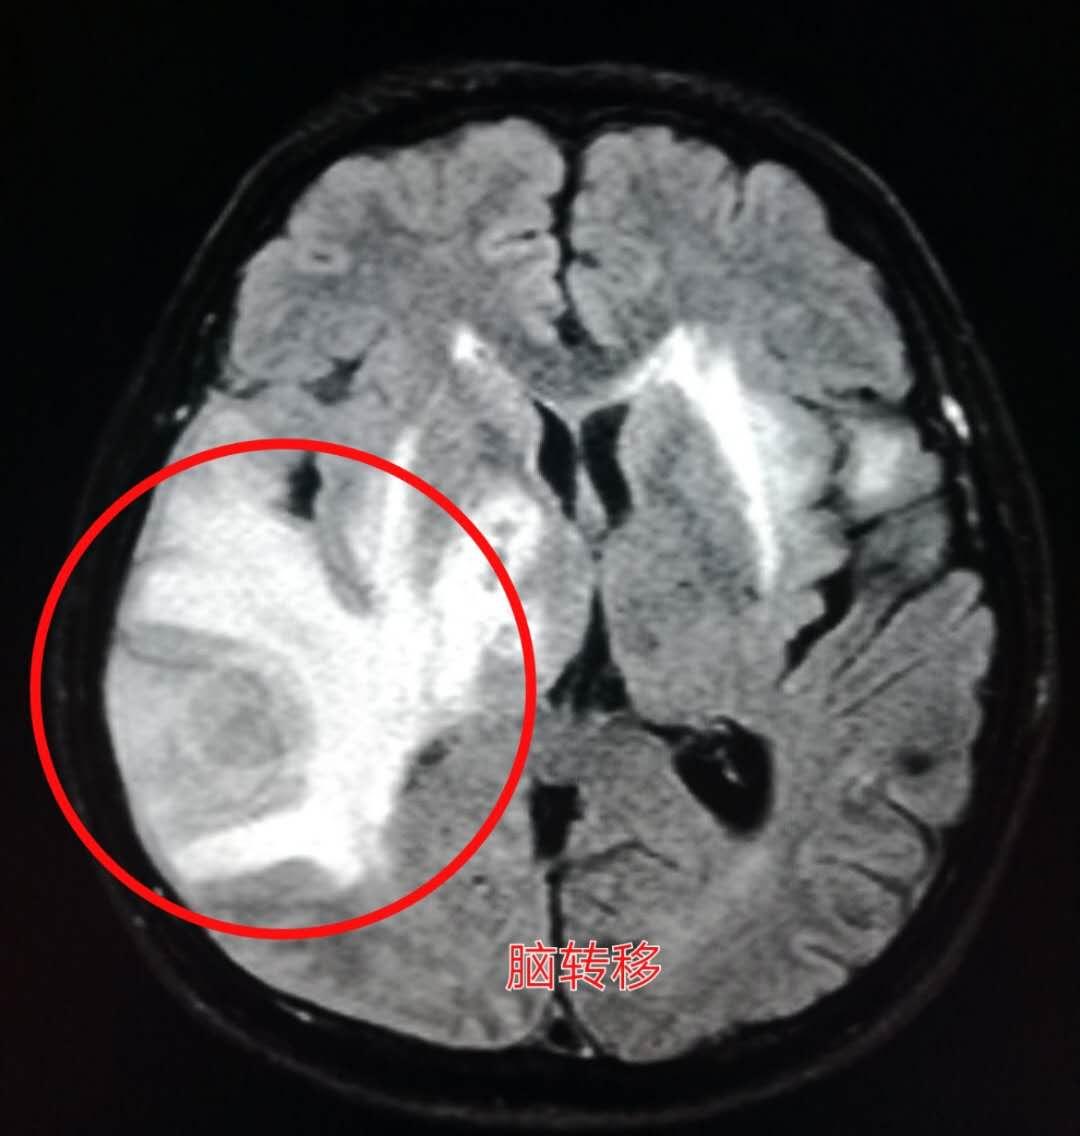

下图就是上周夜班遇到的那位老人,老爷子是一位退休干部,喜欢音乐,在家里弹钢琴的时候突然感觉左侧小指和无名指使不上力,按不动琴键了。

来医院做了脑部核磁共振,发现了脑转移瘤:

紧接着做了胸部CT,证实为右侧肺癌,老人没有任何肺部症状: